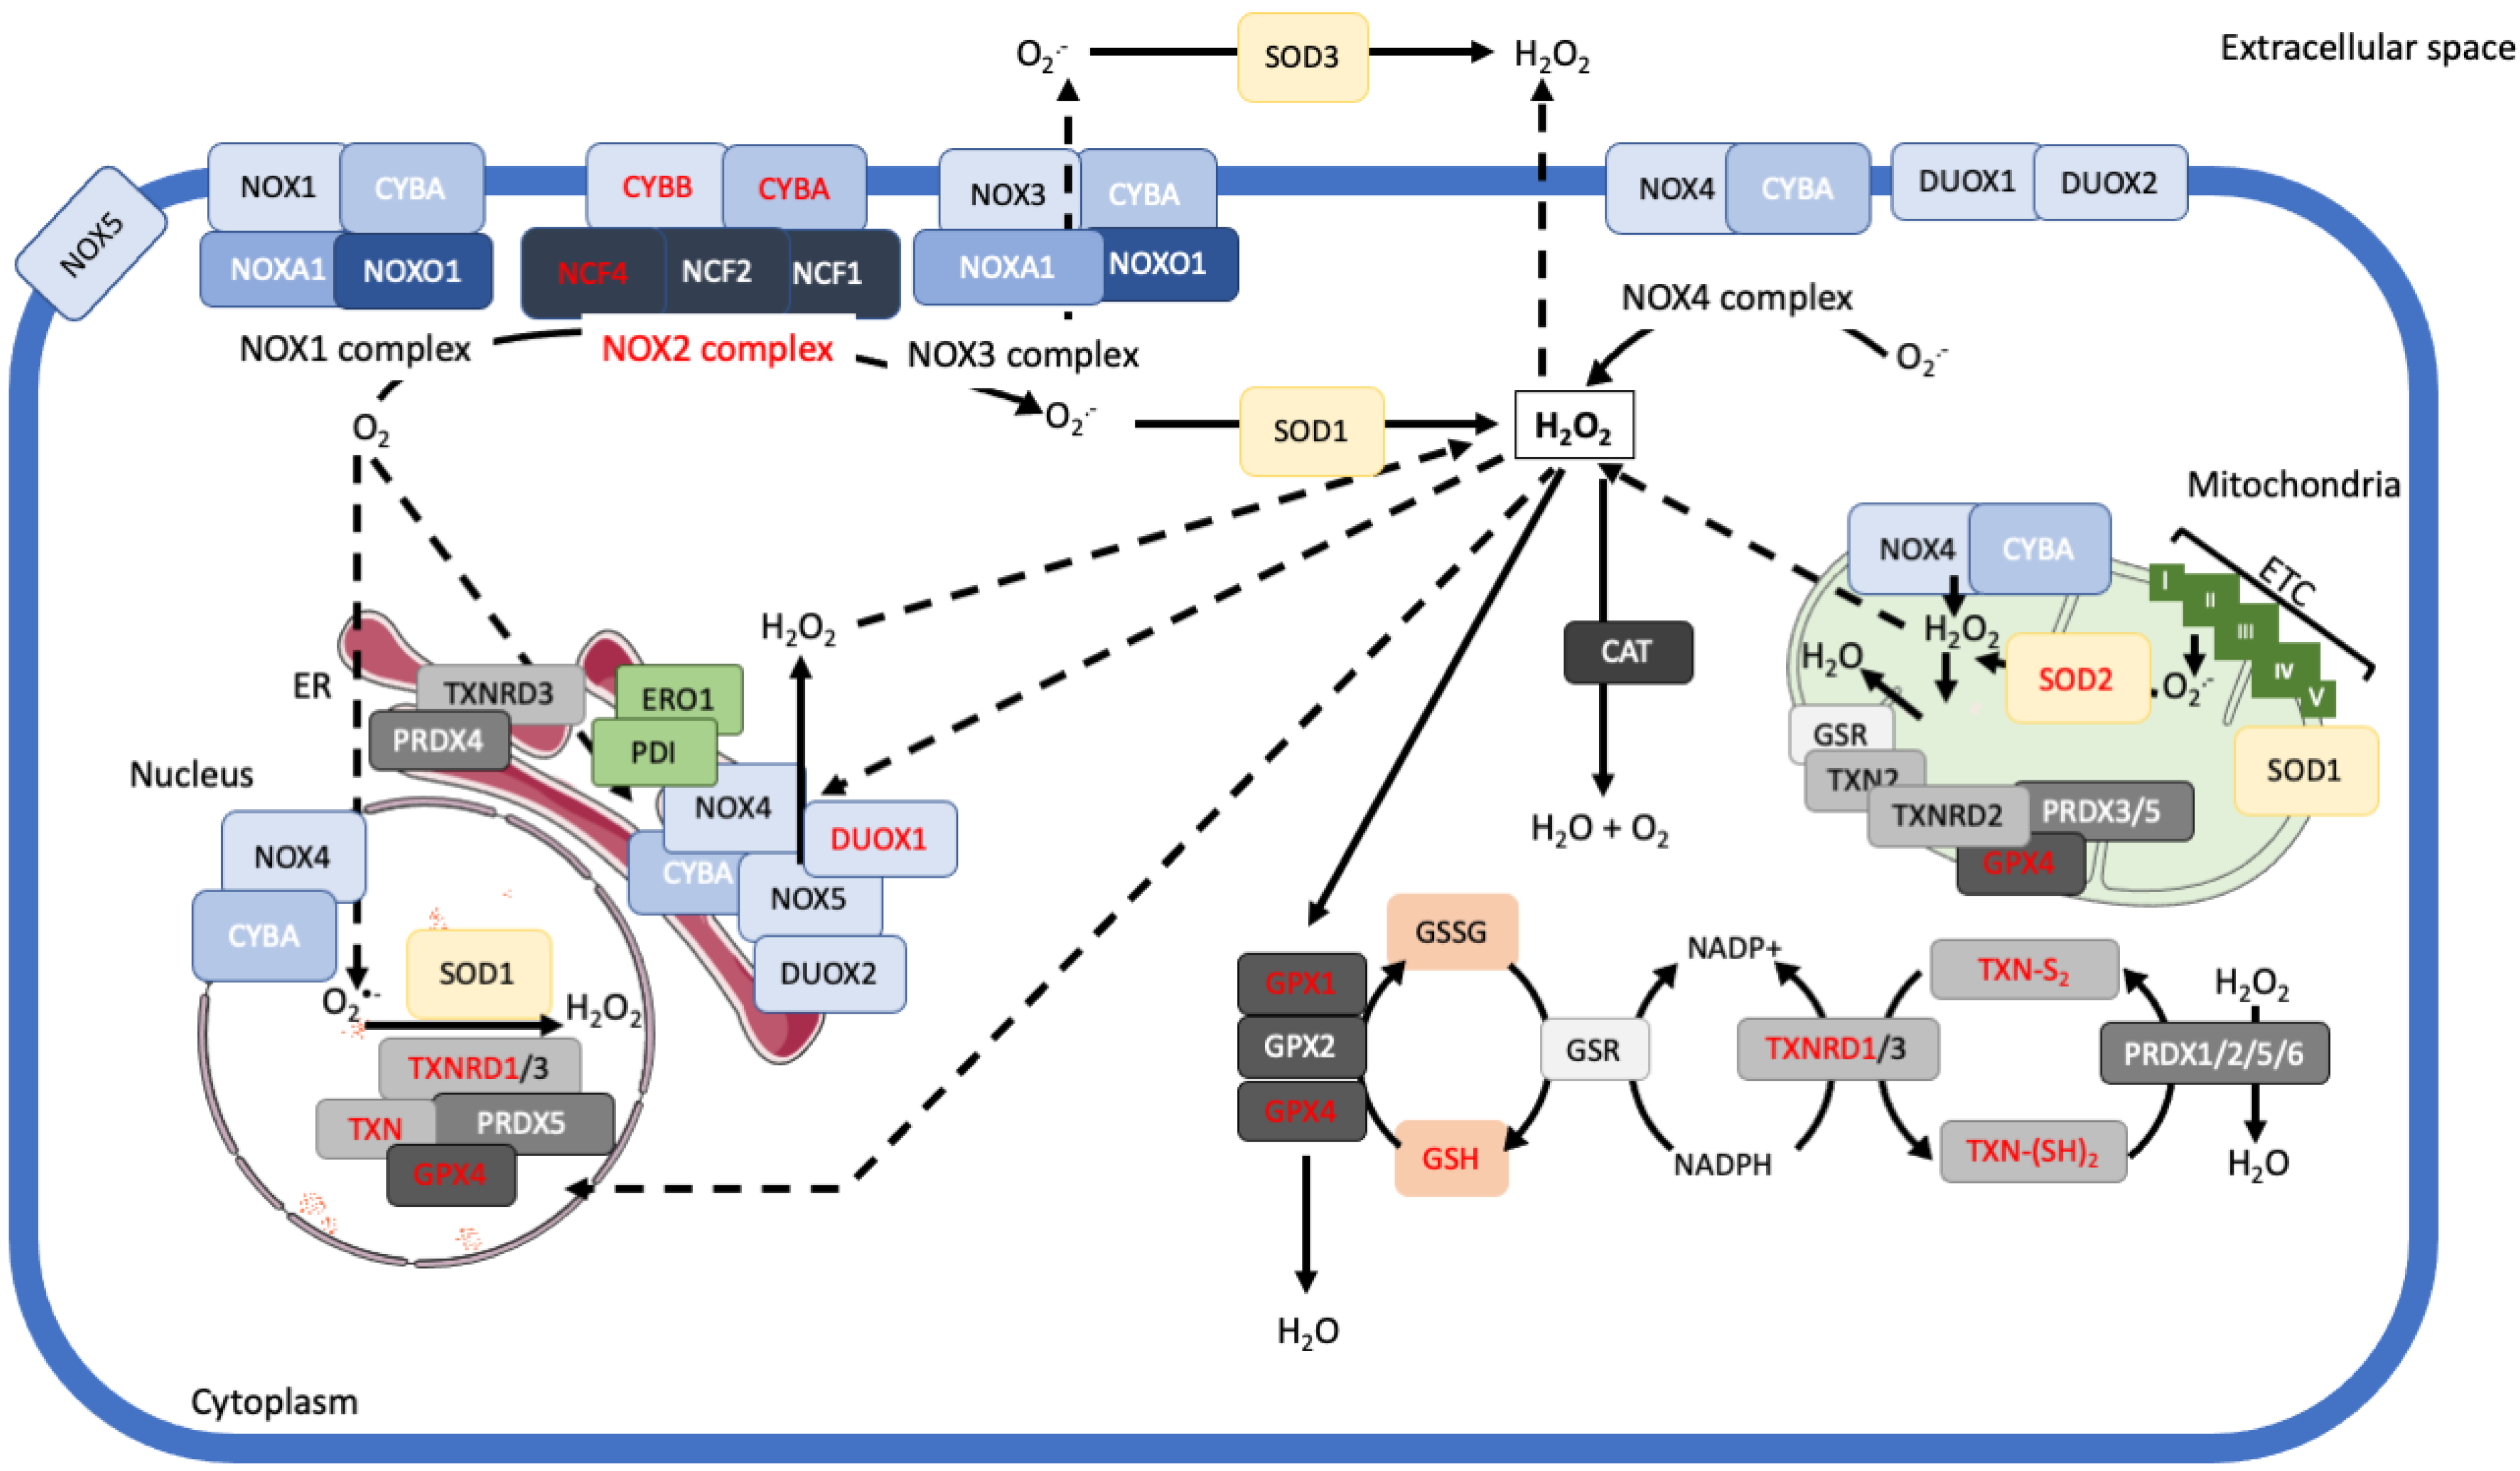

NADPH oxidases: redox regulation of cell homeostasis and。Targeting Reactive Oxygen Species Metabolism to Induce。Paradigm Shifts in the History of Nox2 and Its Regulators。ご覧いただきありがとうございます。サイズMカラー黒2.3回着用しましたが着なくなったので出品いたします。質問等あればコメントしてください。。【GW★SALE】美品!オール本革スエード レザー ジャケットGO WEST。KADOYA K'S LEATHER パンチングレザージャケット Sサイズ。RS TAICHI レザージャケット M